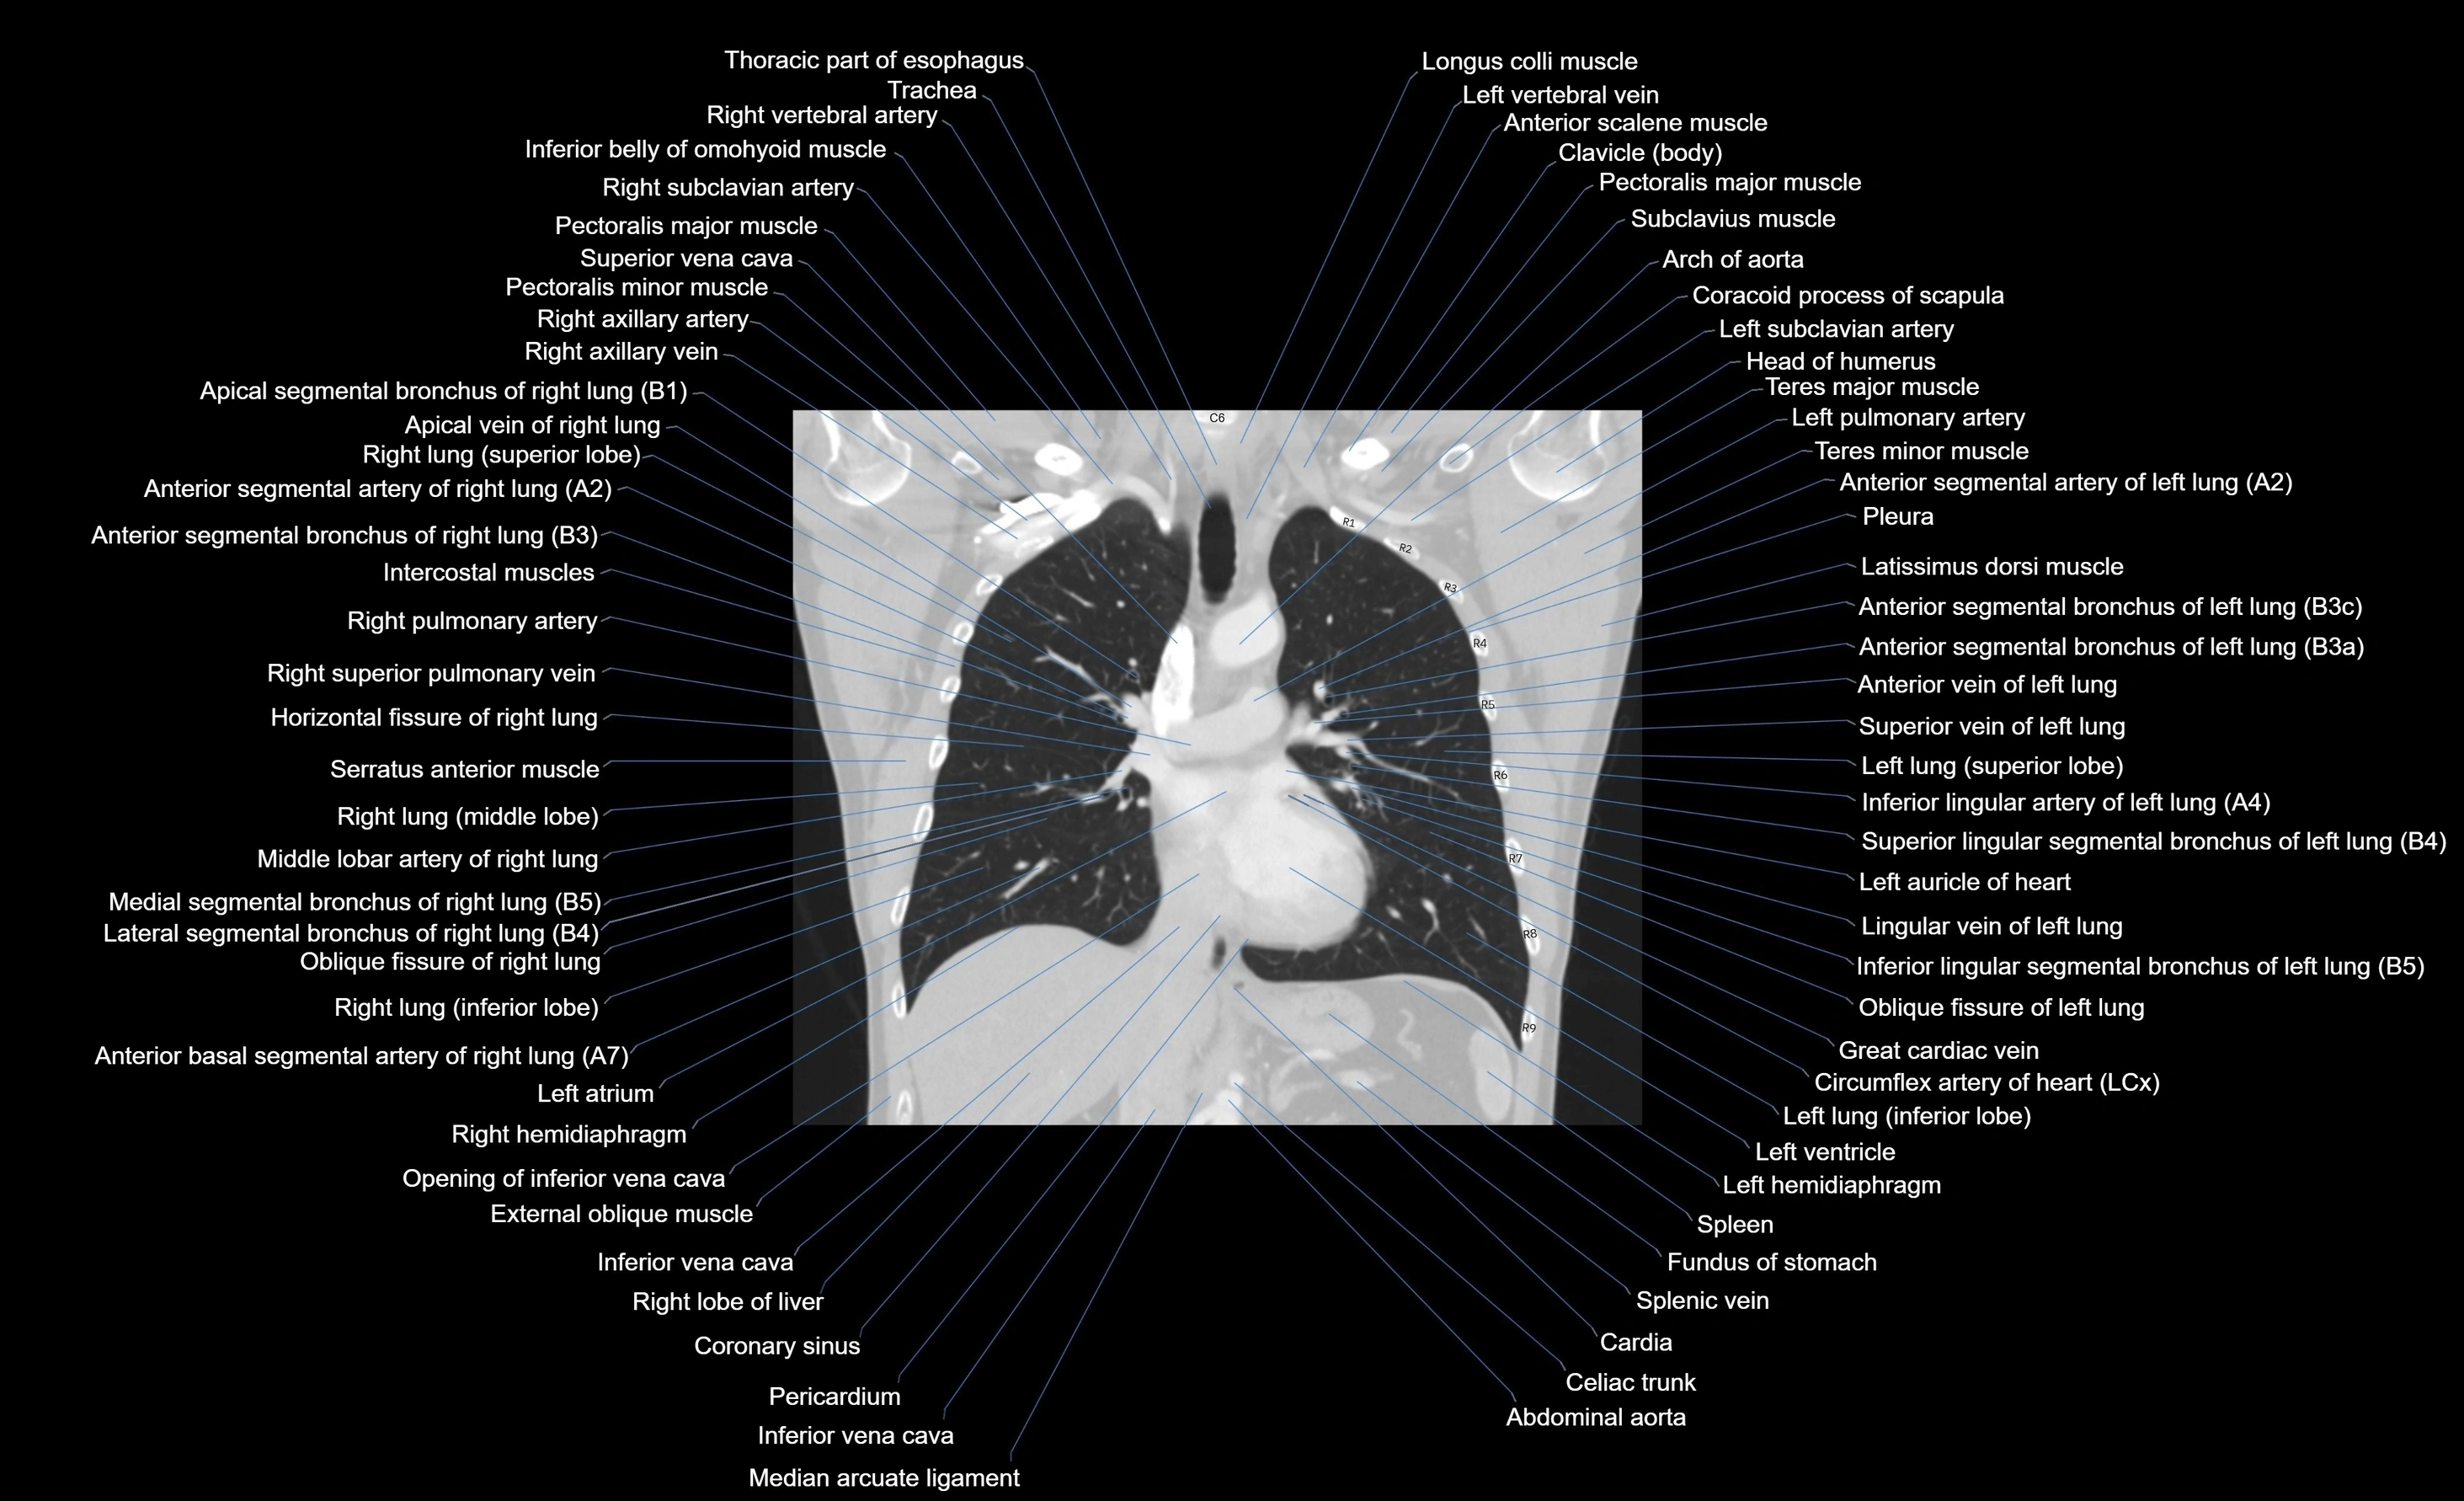

- Abdominal aorta

- Arch of aorta

- Celiac trunk

- Great cardiac vein

- Horizontal fissure of right lung

- Inferior vena cava

- Latissimus dorsi muscle

- Left atrium

- Left hemidiaphragm

- Left lung (inferior lobe)

- Left pulmonary artery

- Left ventricle

- Median arcuate ligament

- Oblique fissure of left lung

- Oblique fissure of right lung

- Pectoralis major muscle

- Pectoralis minor muscle

- Pleura

- Right lobe of liver

- Right lung (inferior lobe)

- Right lung (middle lobe)

- Right lung (superior lobe)

- Right ventricle

- Spleen

- Splenic vein

- Superior mesenteric artery (SMA)

- Superior vena cava